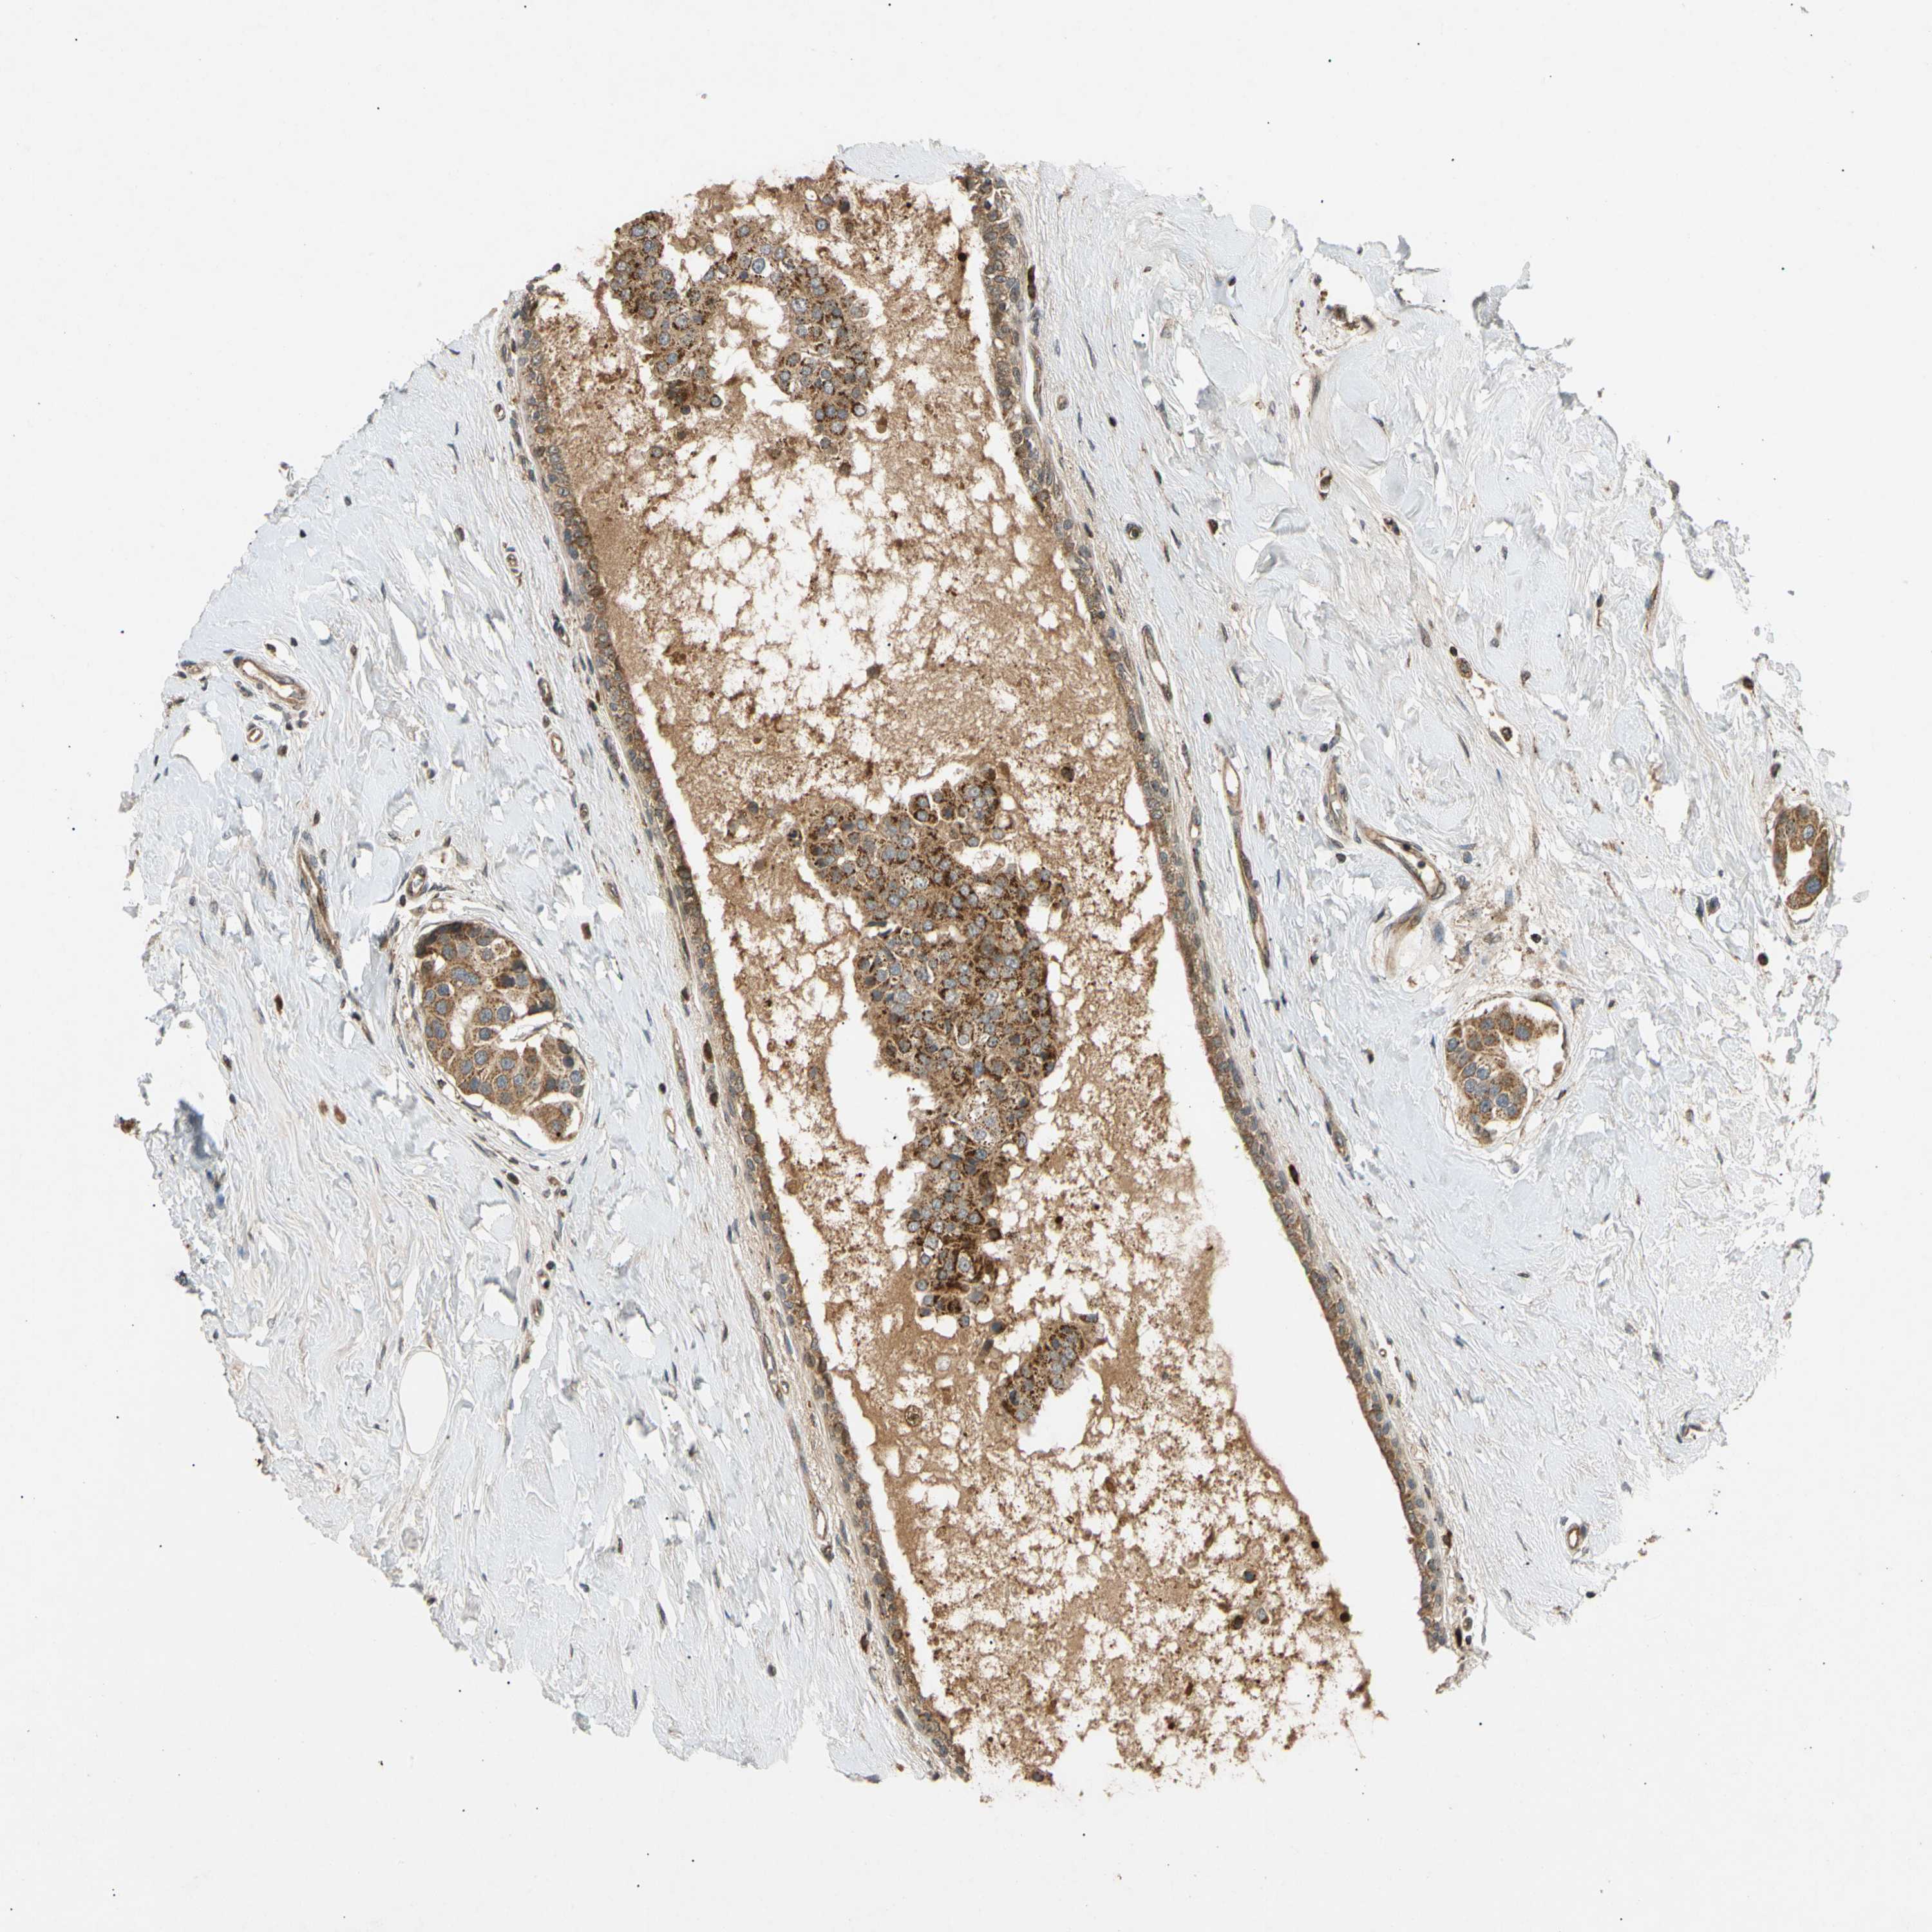

CANCER BREAST CANCER Show tissue menu

BRCA TCGA BRCA VALIDATION PROTEIN EXPRESSION